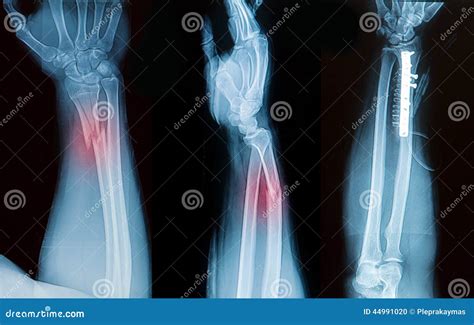

A forearm X-ray is one of the most common diagnostic imaging procedures performed in emergency departments, urgent care centers, and orthopedic clinics. Whether you have suffered a sudden fall, a sports-related injury, or are experiencing unexplained chronic pain, this imaging tool provides doctors with a vital, non-invasive look beneath the skin. By utilizing small amounts of electromagnetic radiation to create images of the bones in the forearm—specifically the radius and the ulna—medical professionals can accurately diagnose fractures, dislocations, and various other structural abnormalities. Understanding the procedure, why it is requested, and what the results mean can help demystify the process and prepare you for your visit to the radiology department.

• Fractures: Whether the bone is broken completely, partially (a hairline fracture), or fragmented (comminuted fracture).

• Alignment: Checking if the broken ends of the bone are touching or if they have shifted.

• Dislocations: Ensuring the bones of the elbow and wrist remain properly seated in their joints.

• fractured forearm x ray